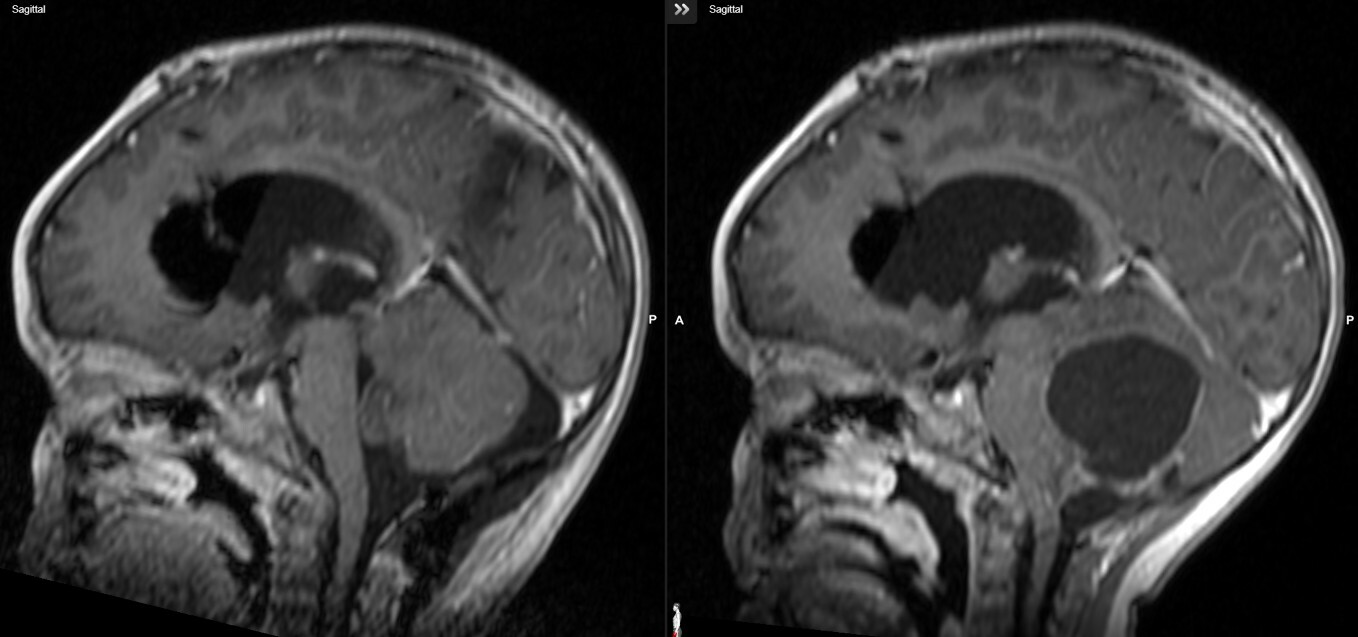

Η ασθενής υποβλήθηκε σε MRI εγκεφάλου, η οποία αποκάλυψε:

- Χωροκατακτητική εξεργασία στον οπίσθιο κρανιακό βόθρο.

- Σοβαρά πιεστικά φαινόμενα στην παρεγκεφαλίδα και το στέλεχος.

- Δευτεροπαθή αποφρακτικό υδροκέφαλο.